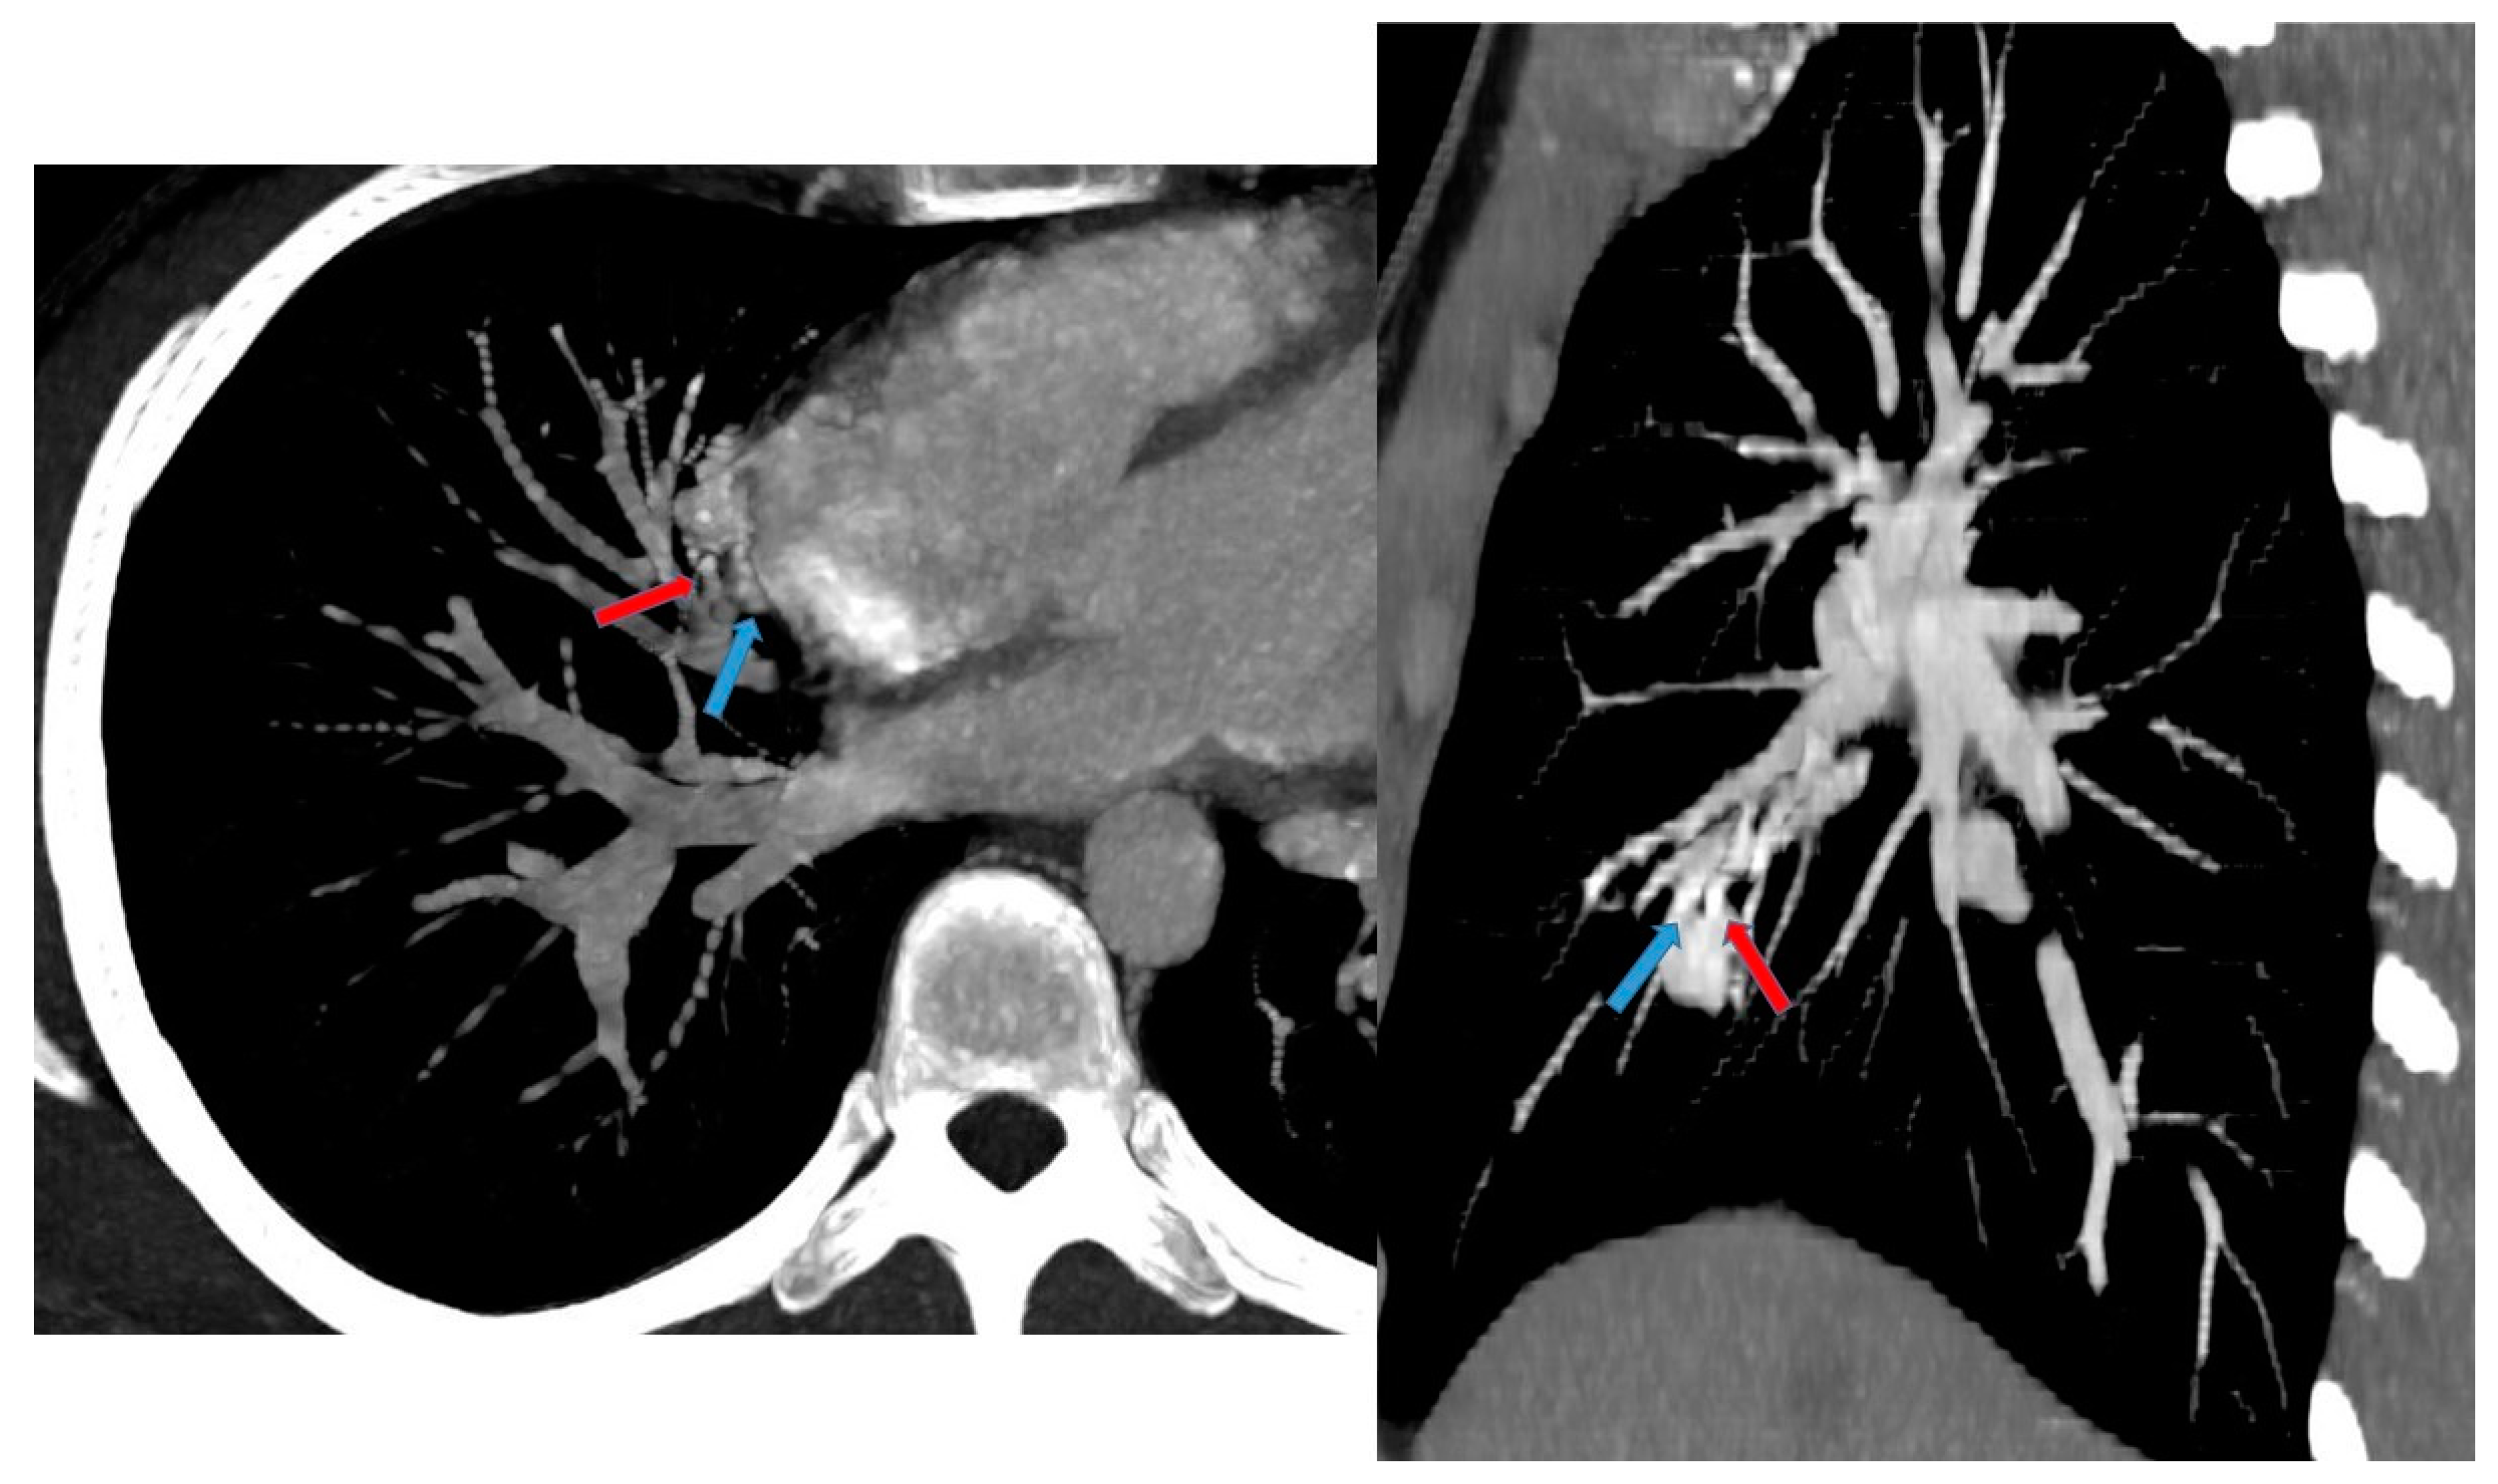

On non-contrast CT, PAVMs typically can be seen as lobulated or serpiginous intraparenchymal masses with soft tissue attenuation. Following the administration of intravenous contrast, these lesions demonstrate marked enhancement. CT may be helpful in the characterization of AVM with complex angioarchitecture, especially using angiography protocol combined with 3D reconstruction [15,32] (Figure 12).

Figure 12.

A 17 year old patient with hereditary hemorrhagic telangiectasis (HHT). CT angiography with maximum intensity projection (MIP) reconstruction shows a lobulated enhancing lesion in the right middle lobe, with a feeding artery (red arrow) and a draining vein (blue arrow), compatible with pulmonary arteriovenous malformation.